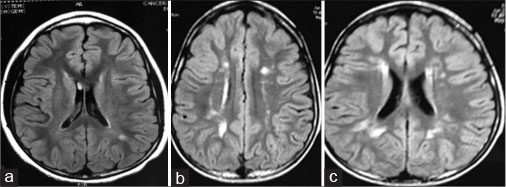

| Figure 3 Images of T2-weighted MRI (brain) for three children with acute lymphoblastic leukemia who showed abnormalities. (a) Grade I: 13-year-old female. (b) Grade II: 8-year-old male. (c) Grade II: 6-year-old male

The white matter areas that were affected are associated with memory, executive functions, and processing speed. Analysis of postassessment data of the three patients revealed a reduced mean score for PIQ, working memory, visual immediate and delayed memory, processing speed, verbal retention, visuospatial ability, attention, planning and fine motor skills, and verbal comprehension, with further decrease in the fourth and fifth assessments as compared to the baseline.

Neuroanatomical deficits, common among childhood ALL survivors, include white matter abnormalities, which may result from the disruption of the myelinization process occurring during childhood because of HD-MTX, which is worsened by whole-brain irradiation. Microangiopathy has also been reported in associated with this treatment. MRI scans performed in this study also revealed abnormalities in brain structure for three children with ALL, and these children had poor performance in PIQ, working memory, visual immediate and delayed memory, processing speed, verbal retention, visuospatial ability, attention, planning and fine motor skills, and verbal comprehension.[35] [36] [37] [38] [39] This could be because of white matter changes in the brain.